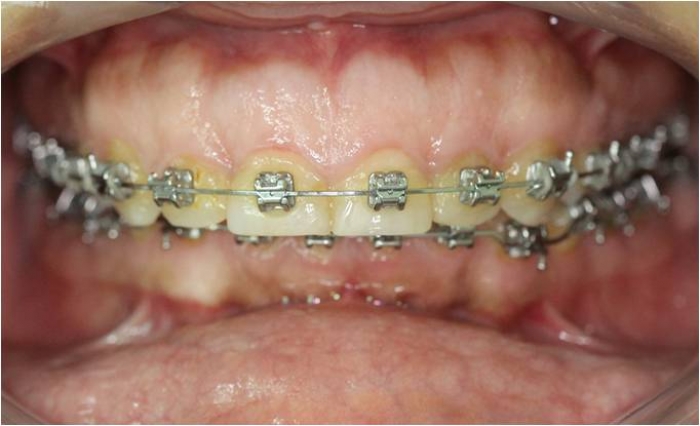

Mordida inicial

Mordida final